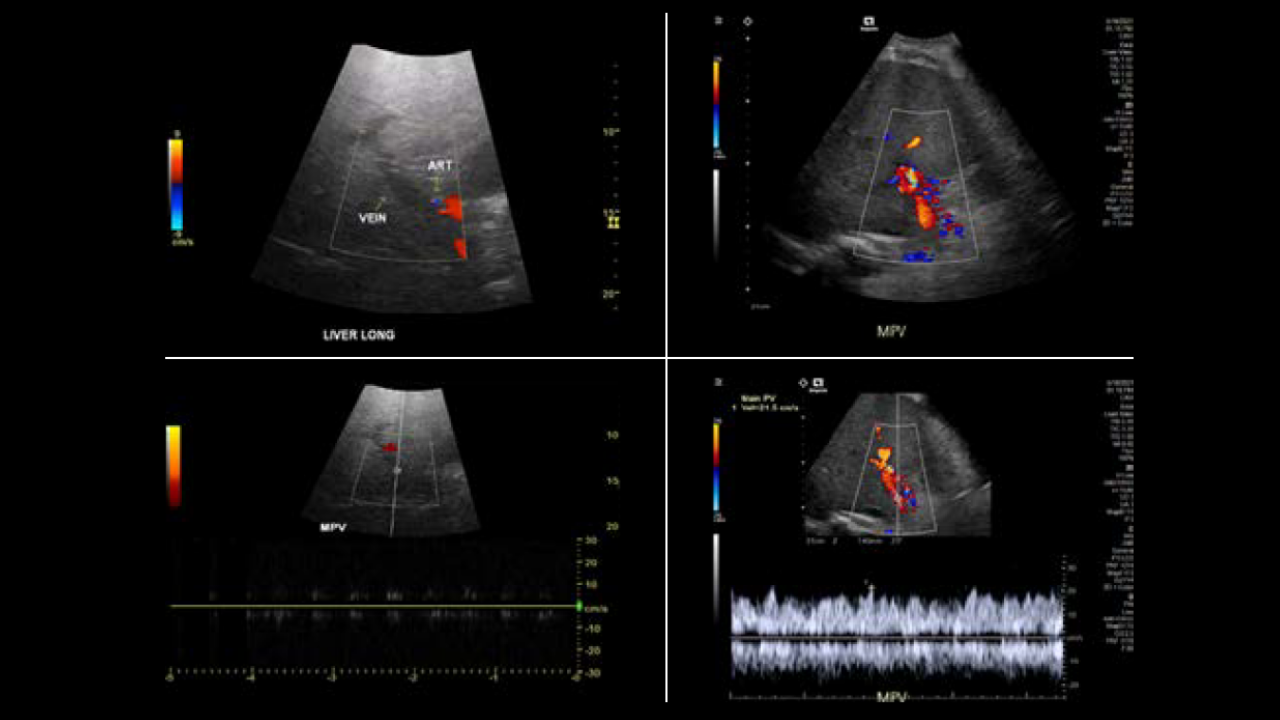

Every patient deserves a definitive ultrasound, even when the exam is difficult. The DAX Deep Abdominal transducer for ACUSON Sequoia brings clarity at depth and consistent visualization of deep anatomy while reducing the force needed to scan.

In high-BMI and technically challenging cases, it helps elevate B-mode and Doppler performance and works seamlessly with advanced applications such as shear wave elastography, Ultrasound-derived Fat Fraction, and contrast-enhanced ultrasound. The result is a gentler exam, clearer answers, and decisions made with confidence.

Radiology departments are often challenged by obesity and conventional technology that can limit diagnostic accuracy due to deep vessels, deep lesions, or severe disease.